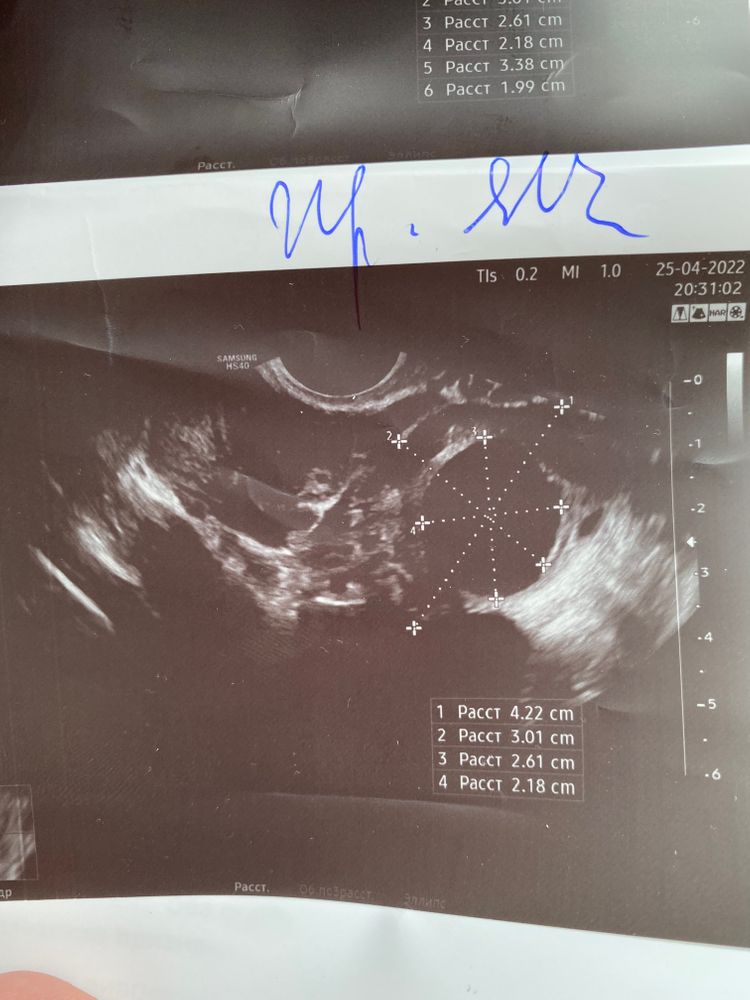

УЗИ И ПЯ ИЛИ ЧТО 😤

Это ДФ а не жт

Знаете, лично я не вижу ЖТ, но вижу фоликулярную кисту или просто большой ДФ. ПЯ не вижу, просто может быть узелок, полипчик, складка, пузырёк воздуха, сгусток кровки и др.

Ну не знаю . У меня такой вот узелочек превратился в плодное яйцо . Только размер был 1'8 мм